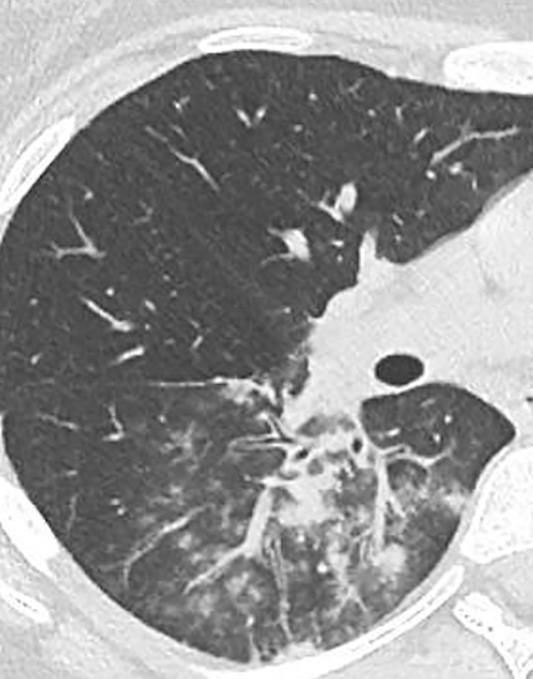

Acute Pediatric COVID-19: CT

21 Imaging of Covid 19 infection in children

3 Phases

Early: "Halo" sign

Local infection

Progressive: Diffuse GGO

Developed: Consolidation

Surr vasc congestion

Inflammation - adj alveoli

Alveoli fill with fluid/cells

COVID 19

• Patchy bilateral GGO, Consolidations or both

• Bilateral & multifocal GGO, +/Consolidations or both

• Halo sign (Early)

• Peripheral and lower lung zone predominance